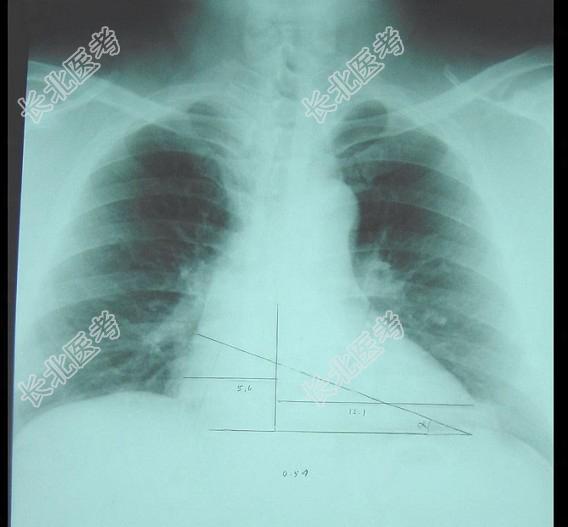

- 单项选择题此心脏正位片描述正确的是 ( )

A、“主动脉瓣型”心脏

B、“中间型”心脏

C、“横位型”心脏

D、“普大型”心脏

E、“二尖瓣型”心脏